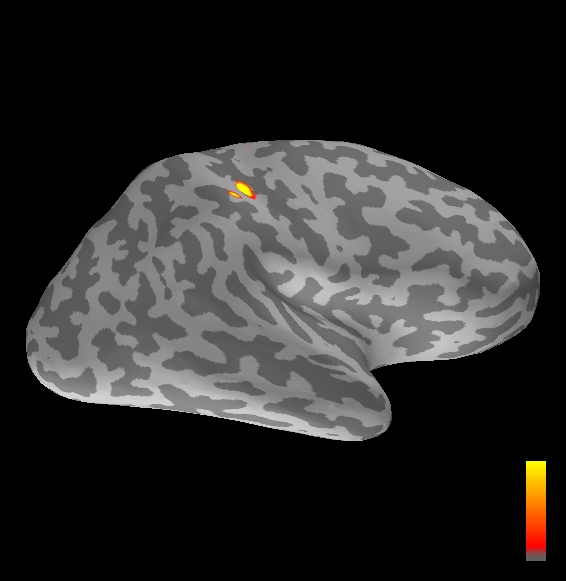

5.2 Results

We applied the ASMC sampler to MEG topographies taken from the above recordings by selecting specific time points according to the previous analysis; the parameter values in the algorithm were the same as those used for the analysis of synthetic data, with the only exception of the noise standard deviation , here estimated from the pre–stimulus interval. In order to validate the results of the ASMC, we also computed source estimates using three other methods: a PF, that approximates the posterior distribution for the current dipoles conditioned on the data up to the selected time point; dSPM, which is based on a distributed source model with an –prior, and consists in normalizing the Tikhonov regularized solution by the noise standard deviation; and sLORETA, which is similar to dSPM but is claimed to have a smaller localization bias. Figure 4 shows the results at , and ms after the stimulus onset. The results are visualized on a computer representation of the brain obtained by “inflating” the cortical surface: gray levels contain the anatomical information, light gray representing gyri and dark gray representing sulci; the activity estimate is coded in color scale, increasing from red to yellow. Importantly, this visualization allows activity in the sulci to be clearly visible; on the other hand, since neighbouring volumes may be moved apart by the inflation process, distinct activity regions are often due to underlying volumetric masses that are very close to each other.

Before describing the results, let us comment on the qualitative difference between the images produced by the ASMC sampler and the PF, on the one hand, and those produced by dSPM and sLORETA, on the other. First of all, we point out that all the quantities shown in the images of Fig. 4 are somehow related to the probability of activation at specific locations. Indeed, for both the ASMC and the PF we plot the approximation of the intensity measure (3.8); for any single grid point, this value can be interpreted as the probability of a dipole being at that location, while it integrates, over a given volume , to the mean number of dipoles within . As for dSPM, the represented quantity is a statistical value that is –distributed under the null–hypothesis of zero activity; as a direct consequence, it also yields a probability of activation, which is however not constrained to be dipolar. Similar considerations apply to sLORETA, although with a different statistical distribution. Importantly, the representation of the results is clearly affected by the setting of the visualization threshold. Owing to the explained differences between the methods, it seems reasonable to use a different value for each method. At the same time, since the plotted quantity is a probability of activation, it seems right to use the same thresholding for different time points. In this connection, the thresholds in Fig. 4 have been chosen by hand following the guidelines just outlined.

Using the same thresholding and parameters at different time points makes the four methods respond differently to the diverse intensities of the different sources. Whenever a stronger source is active, both sLORETA and dSPM will tend to produce widespread estimates, while weaker sources will be represented as small active areas. The behaviour of the ASMC and of the PF is the opposite: a stronger signal will lead to a precise localization of a dipolar source, and then to a focal marginal distribution for the location; a weaker signal will translate to higher uncertainty on the source position, and therefore a more widespread posterior map.

The phenomenon just described is indeed clearly visible in Figure 4. At ms, all the methods correctly identify the rather strong activation in the contra–lateral primary somatosensory cortex: the ASMC and the PF provide very focal maps, while dSPM and sLORETA provide compatible widespread estimates; dSPM also exhibits a more posterior peak which does not fit with the commonly agreed models of the response to median nerve stimulation; this may be due to the formerly described brain inflation.

At ms, the ASMC localizes two sources, one in the right hemisphere and a weaker one in the left hemisphere; these sources appear to be compatible, for timing and location, with the Posterior Parietal Contra and Parietal Opercular Ipsi described in Mauguiere et al. (1997). The PF finds the very same source in the right hemisphere, but it estimates no dipoles in the left one. Such discrepancy between these two methods, which are based on the same source model, is possibly due to two facts: first, thanks to its iterative nature, the ASMC is likely to explore the state space more thoroughly and is therefore more suited to identify weak sources; second, the log–uniform prior on the strength of the dipole moment in the ASMC has a wider range than the corresponding Gaussian prior in the PF. Slightly different results are provided here by dSPM and sLORETA. The activity estimate computed by dSPM seems very similar to that of ms, having the same spatial distribution with a weaker intensity. The estimate of sLORETA in the right hemisphere includes that of the ASMC and of the PF. Neither dSPM nor sLORETA find significant activity in the left hemisphere.

At ms, the ASMC localizes again two sources: a stronger one in the right primary somatosensory cortex, and a weaker one in the left posterior frontal area. Both of them seem to be compatible, for timing and location, with the results in Mauguiere et al. (1997), the left dipole corresponding to the Frontal Ipsi source. Once again, the other three methods only recover the stronger source.